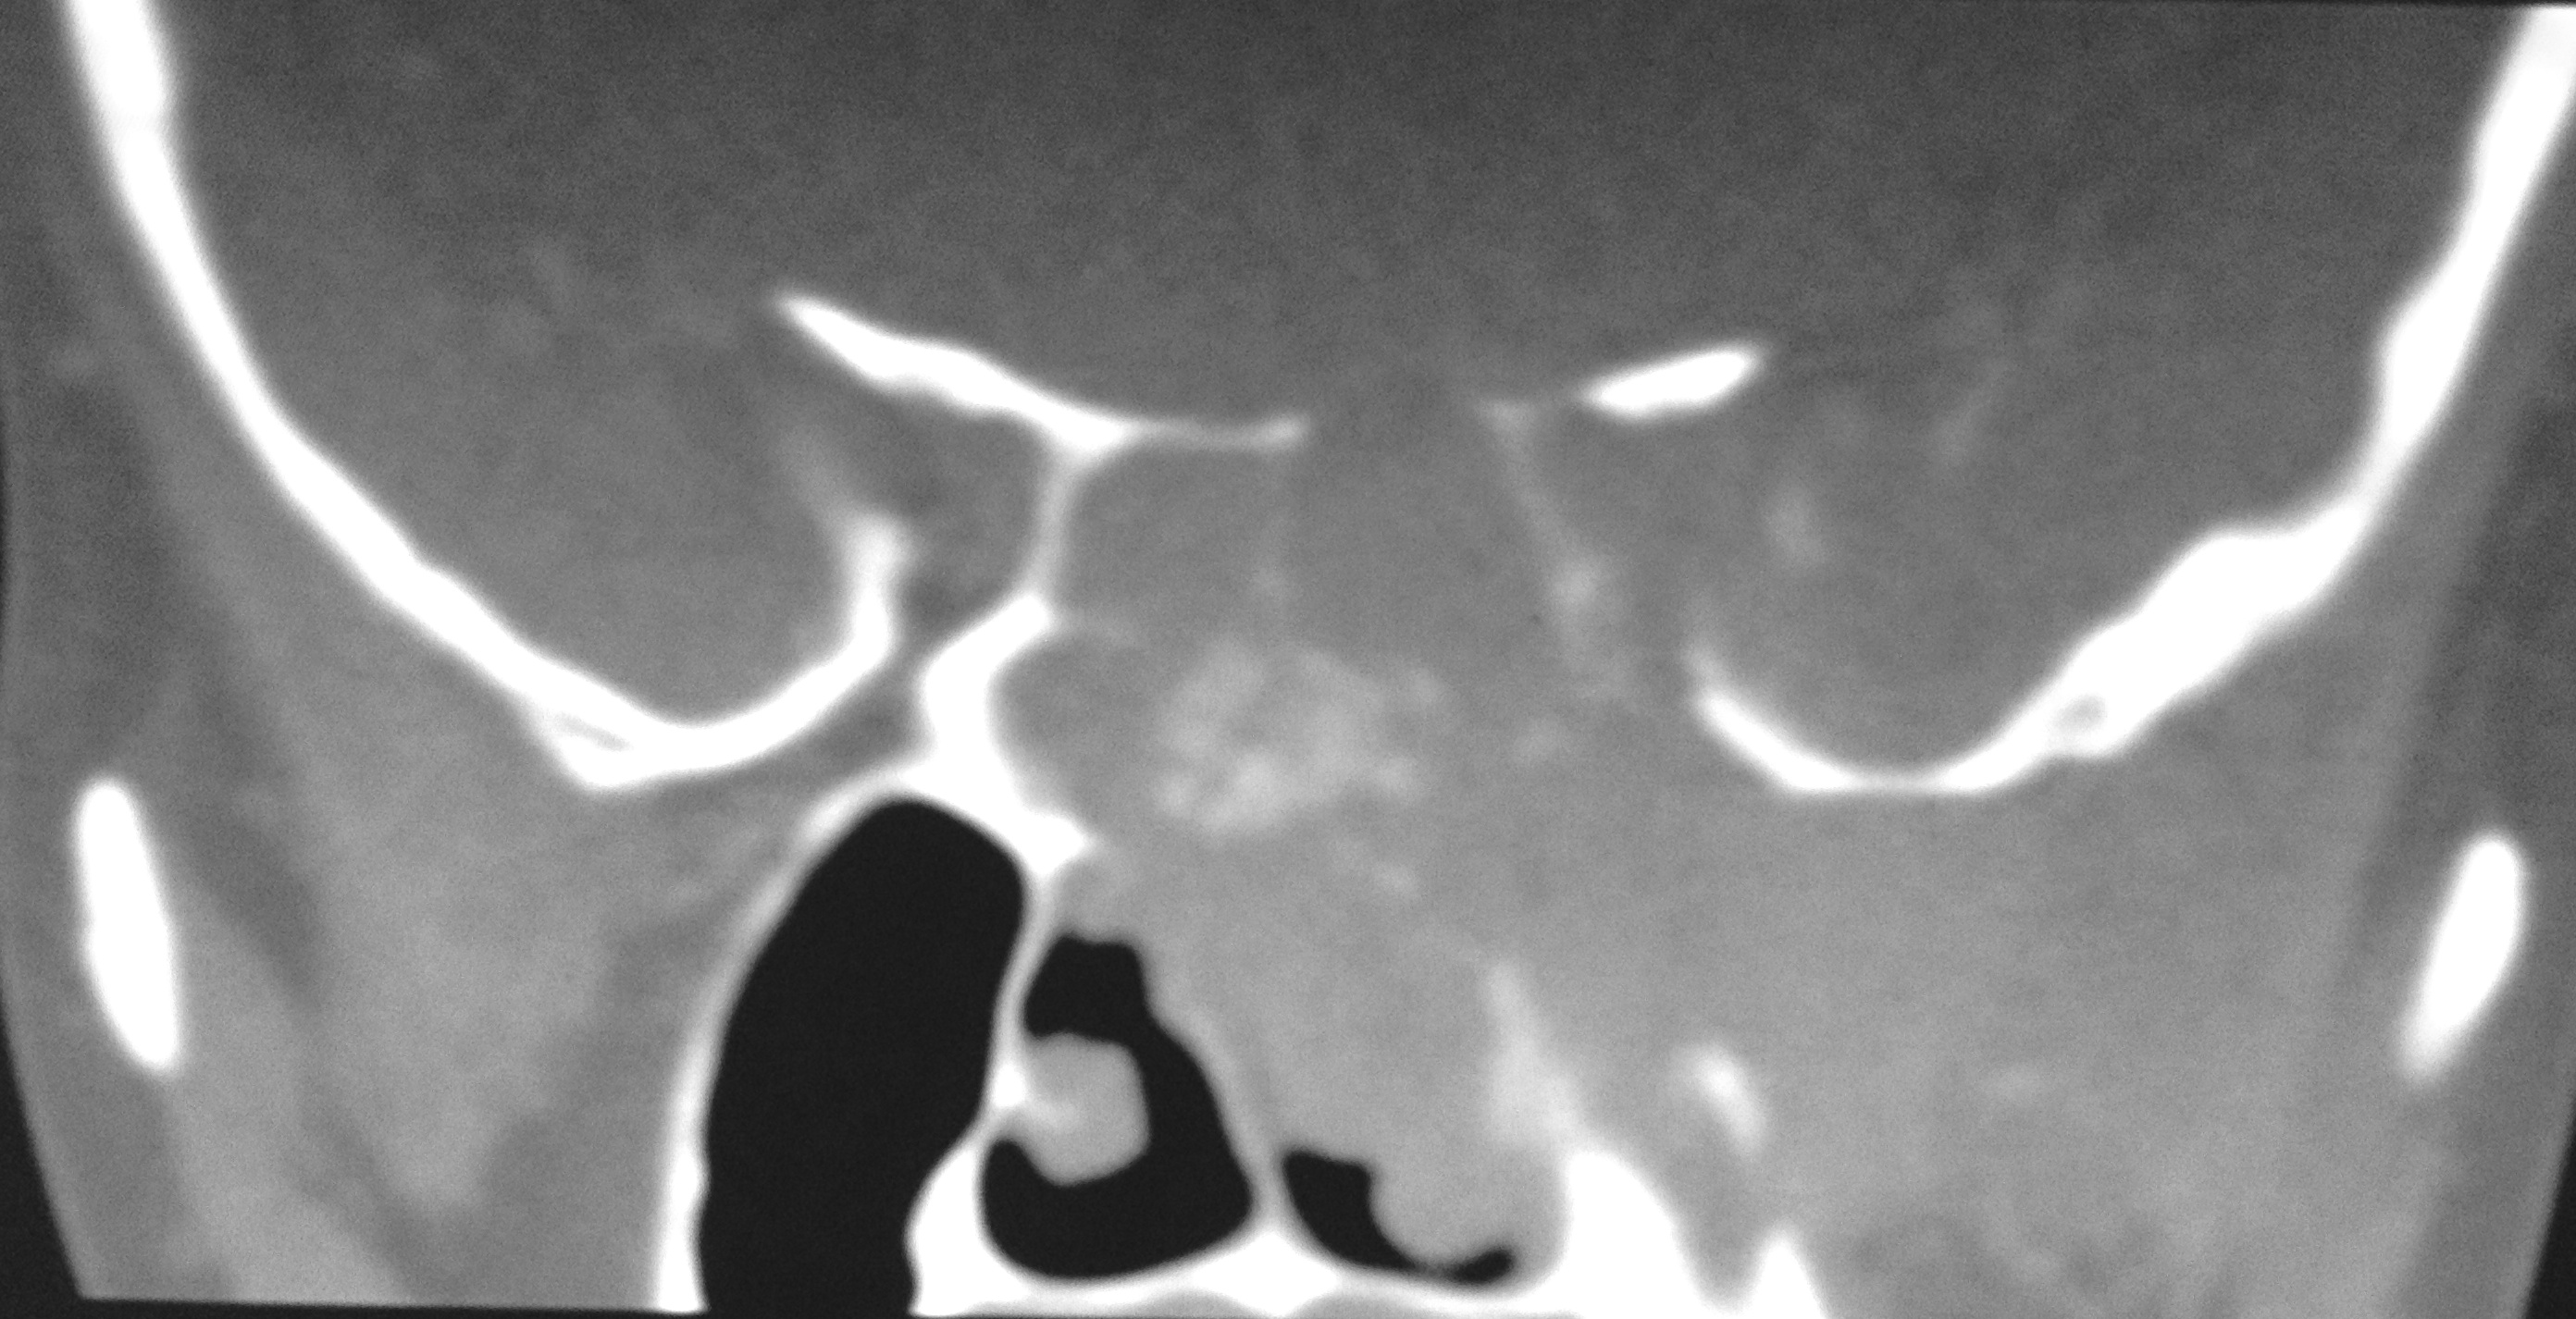

Nasopharyngeal carcinoma is a malignant disease and is more common in males than in females with M:F ratio of 3:1. It has a bimodal peak at 16-20 and 46-50 years of age. Orbital involvement is seen in 3.2% and bilateral orbital invasion occurs in 0.7% of patients with nasopharyngeal carcinoma. Imaging has significant role in detecting the early nasopharyngeal carcinoma, tumor staging, involvement of lymph node, monitoring the patients after the therapy, to detect recurrence and radiation associated changes in the soft tissue and bone. We report a case of aggressive nasopharyngeal carcinoma in 22 years old male who presented with rapidly progressive diminution of vision.